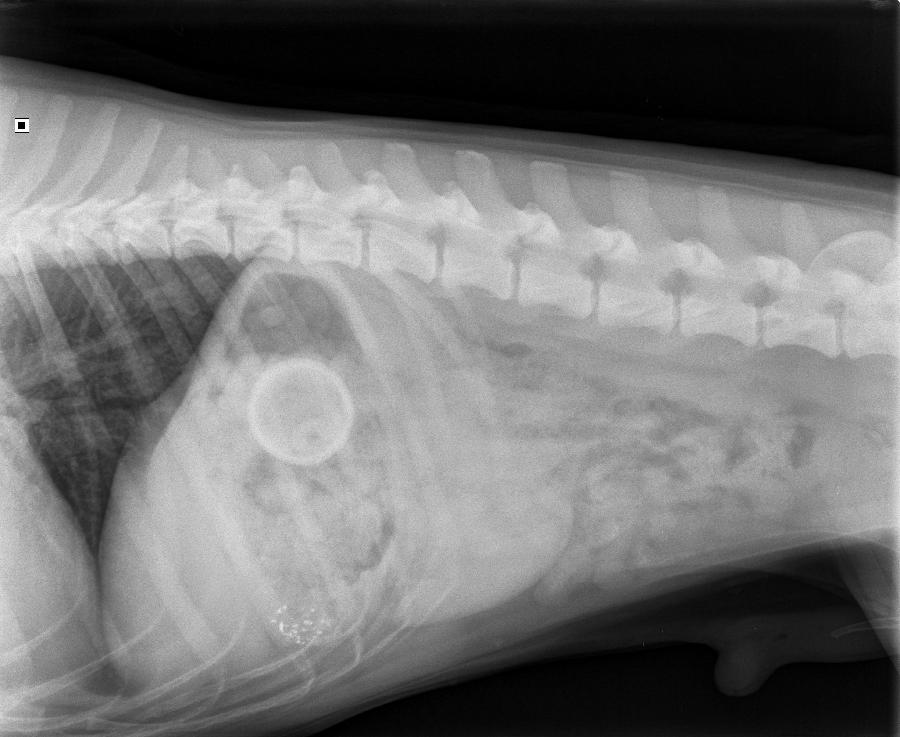

Op 5 maart 2020 werd de kruising Appenseller x labrador Brasso aangeboden op de praktijk. Brasso braakte en de eigenaar miste een klein tennisballetje.

Op de foto was goed te zien waarom brasso braakte, én waar het balletje was. We hebben Brasso geopereerd en het balletje uit de maag gehaald. Brasso werd vlot wakker en is heel goed hersteld van de ingreep. Of Brasso hiervan geleerd heeft? Dan weten we (nog) niet...

Op de röntgenfoto is het balletje goed te zien